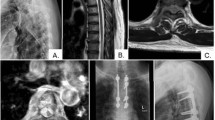

The epidural presentation in eight patients was heralded by motor signs (paraparesis and plegia), in one by a lesion of the posterior columns of the spinal cord (ataxia), and in three by pain. One patient was free of complaints and symptoms. The affected epidural area was diagnosed previously by myelography and computerized tomography (CT), and later by magnetic resonance (MR), over the course of which the location was verified as thoracic in eight patients, cervical in one, and lumbar in four. The authors recommended surgical intervention in 9 out of 13 cases, in seven cases of Hodgkin's and six cases of non-Hodgkin's lymphoma. Seven patients were treated for recognized manifestations of malignant lymphoma while six were diagnosed by intraoperative-histological examination.

The decompression operations for tumors resulted in limited improvement in seven patients (reduction in pain and return of ability to walk). Four patients were not operated on, two of which had significant improvement in their neurological symptoms. Paraparesis remained unchanged in one patient. One patient remained symptom-free. The authors emphasize the importance of interdisciplinary consultation and weighing individual priorities in the indications for operation on epidural ML.